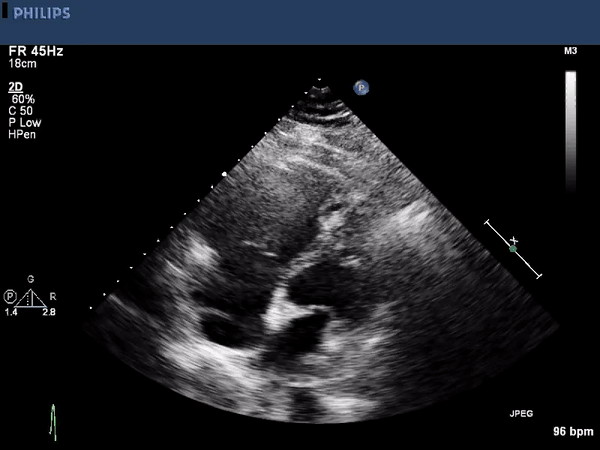

The echocardiographic images above show a large right ventricular

thrombus. The first image is a parasternal long axis view highlighting

the right ventricular inflow tract. A mobile thrombus is seen near the

anterior border. The other two images are using an apical approach

showing the right and left ventricle. Again a mobile the thrombus is

seen within the right ventricle. Contrast is used to enhance the

thrombus borders.